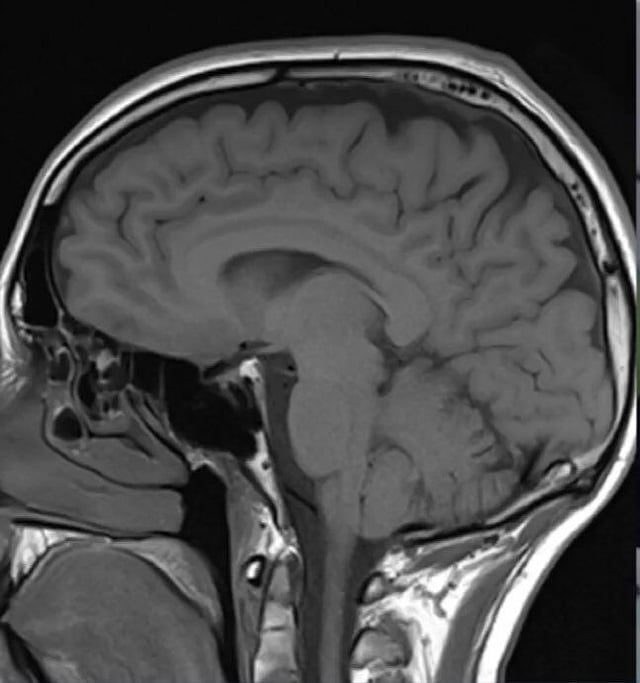

Representation image of a Human Brain  IANS

New York, Jan 13 (IANS) Researchers have discovered that SARS-CoV-2 can directly infect the central nervous system and have begun to unravel some of the virus's effects on brain cells.

The study, that used both mouse and human brain tissue, indicates that SARS-CoV-2 can affect many other organs in the body, including, in some patients, the central nervous system, where infection is associated with a variety of symptoms ranging from headaches and loss of taste and smell to impaired consciousness, delirium, strokes and cerebral haemorrhage.